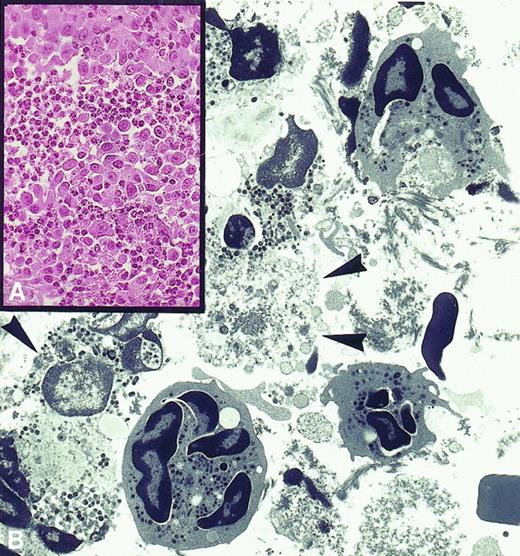

Paracrine release of IL-2, IL-4, IL-12, and TNF-α induced prompt tumor rejection (Figure 2A) marked by the formation of areas of colliquative necrosis typically associated with a massive presence of degranulated PMNs with exocyted granules in close contact with tumor cells displaying ultrastructural signs of irreversible damage (Figure 2B). This indication of direct killing by PMNs was particularly evident in the presence of paracrine IL-2 and TNF-α.

PMN-induced tumor destruction.

(A) Rejection area of subcutaneously injected tumor cells engineered to release IL-2 is massively infiltrated by polymorphonuclear leukocytes (× 630). (B) Electron micrograph showing that these are neutrophils at various stages of disorganization and that their exocytosed granules are in close contact with severely damaged or necrotic tumor cells (× 2750).